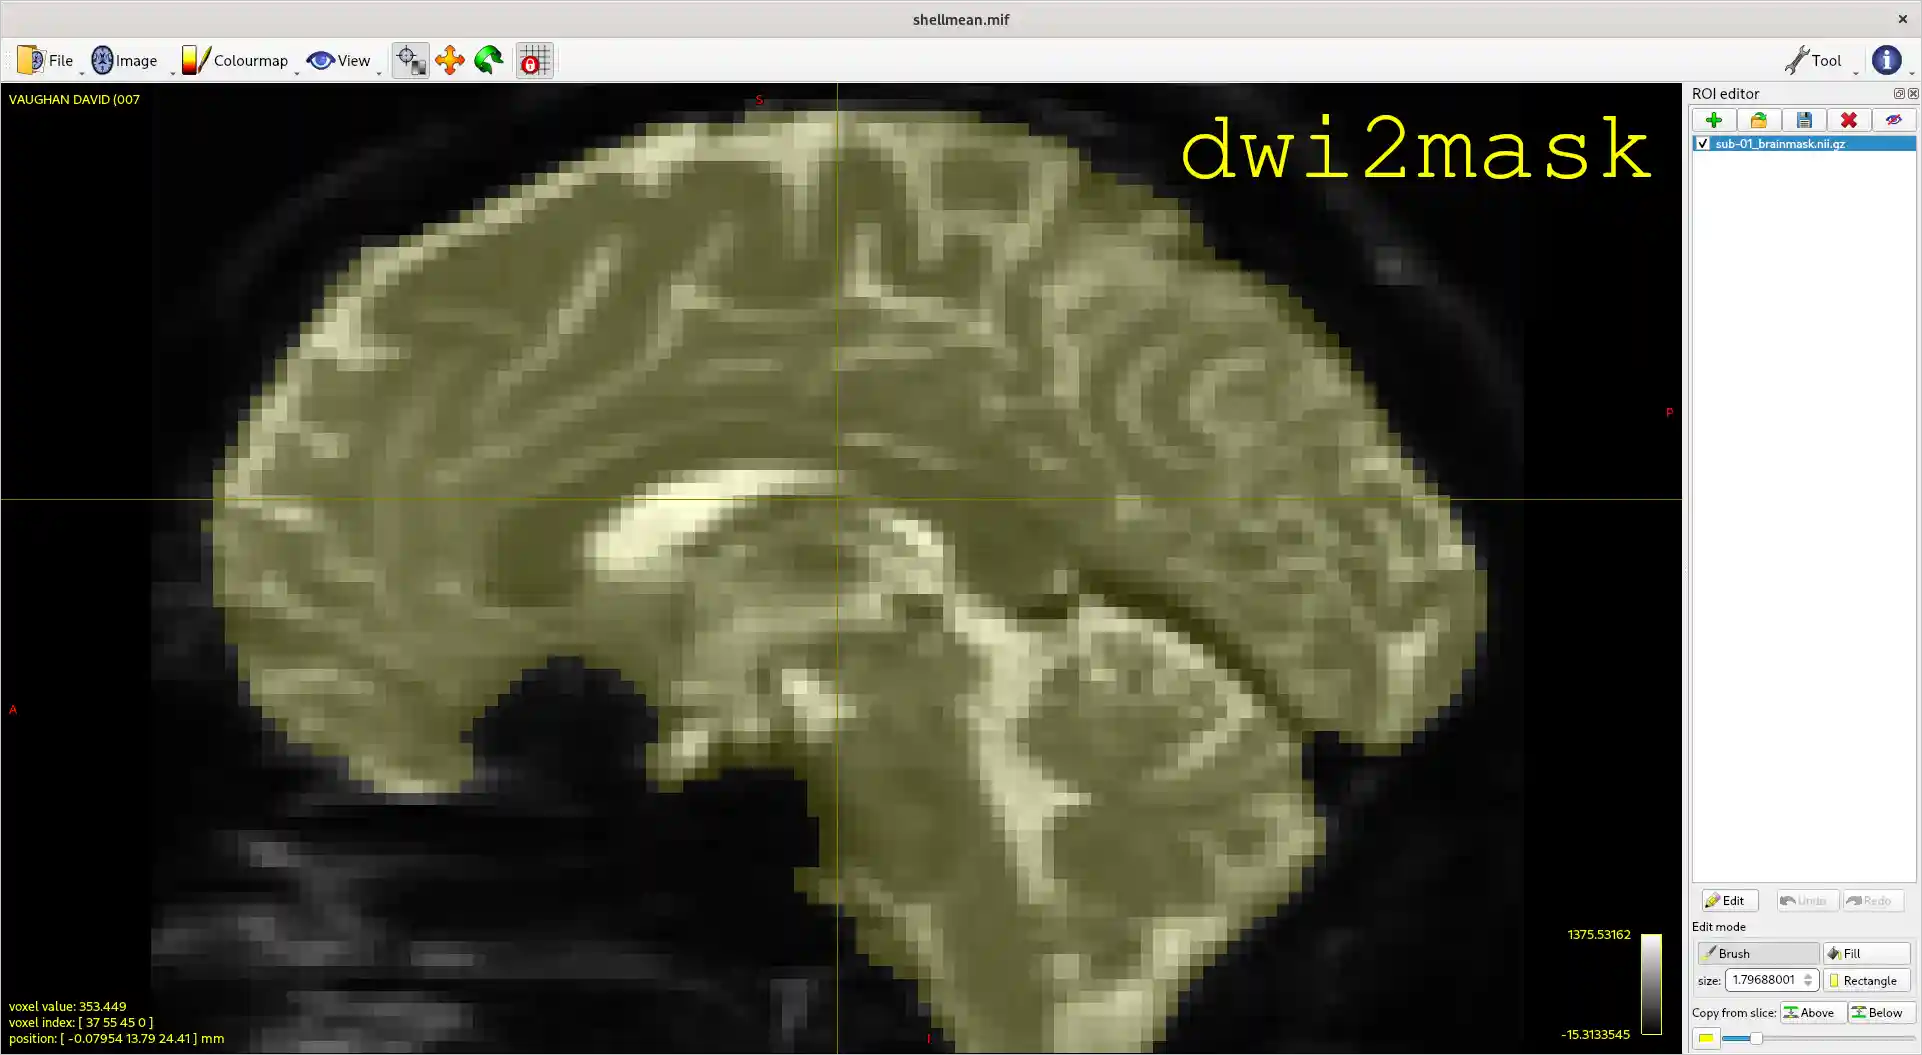

Diffusion MRI brain masking ("dwi2mask")

Deriving a binary brain mask from diffusion MRI data in an automated fashion can be deceptively challenging. This project aims to provide a standardised interface to multiple different algorithms for performing this task, and incorporate it into the MRtrix3 software.